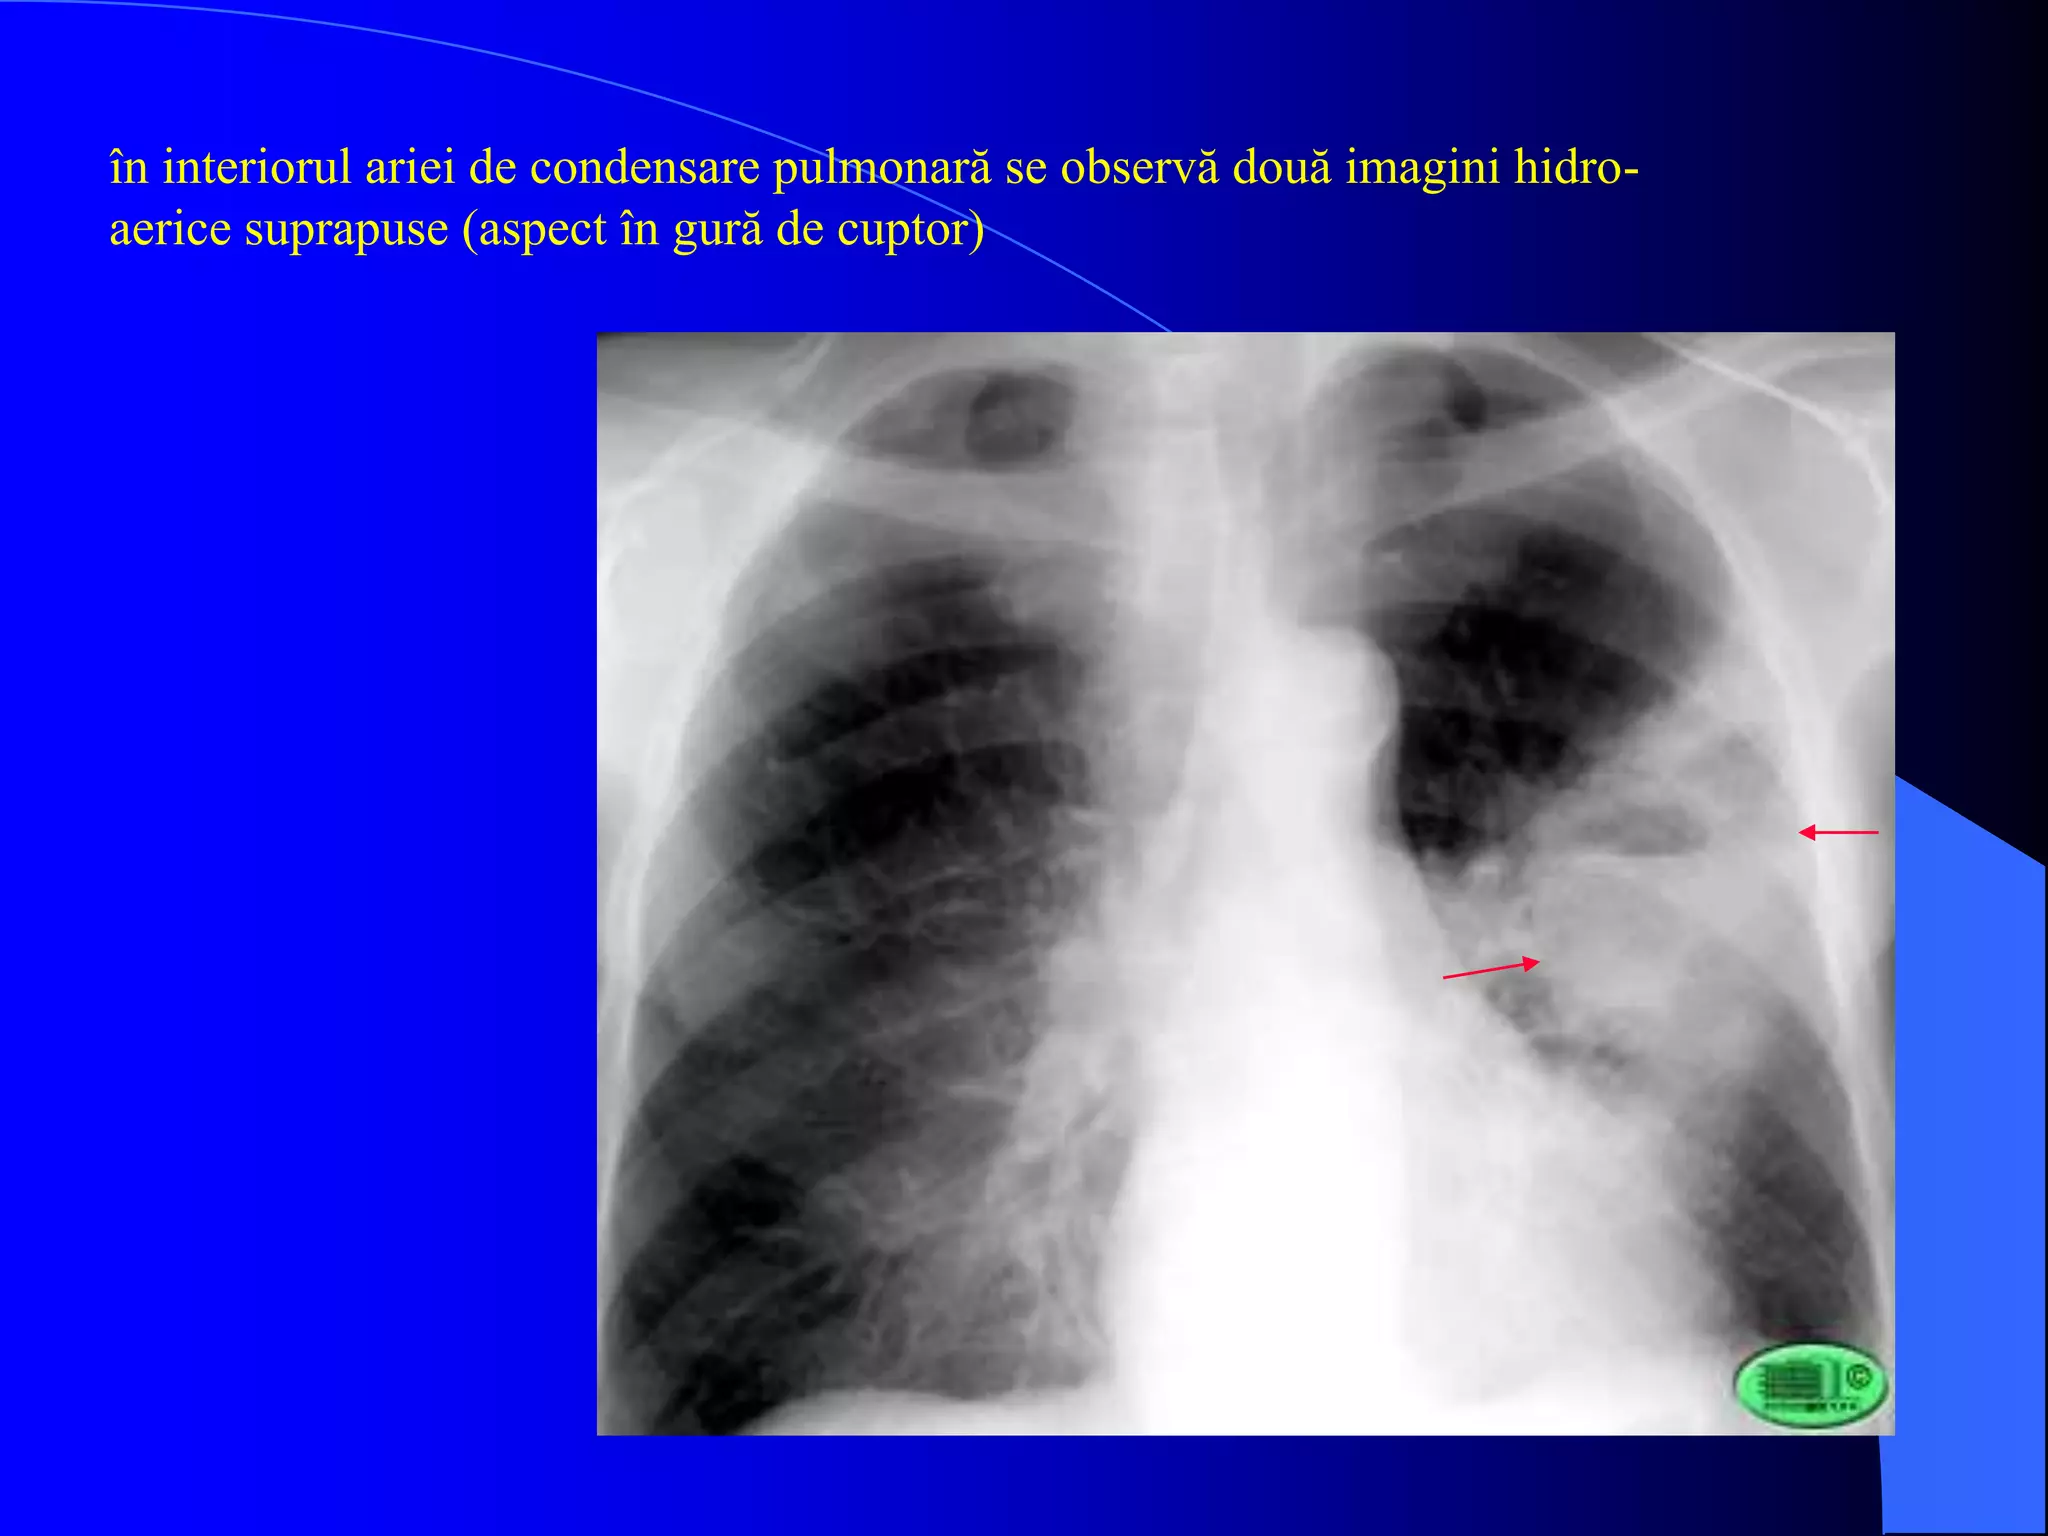

Ex. radiologic

- faza de supuratie inchisa: focar de condensare, mai opac central, nu respecta scizurile

- faza de supuratie deschisa (“claritati in focar”): imagine “in gura de cuptor”

studiul bronhiei de drenaj

abcese pulmonare în faza de constituire

- acelaşi caz prezentat anterior; imagine hidro-aerică localizată în lobul superior

drept

- aspect dupa vomica (săgeată)

în interiorul ariei de condensare pulmonară se observă două imagini hidro-

aerice suprapuse (aspect în gură de cuptor)